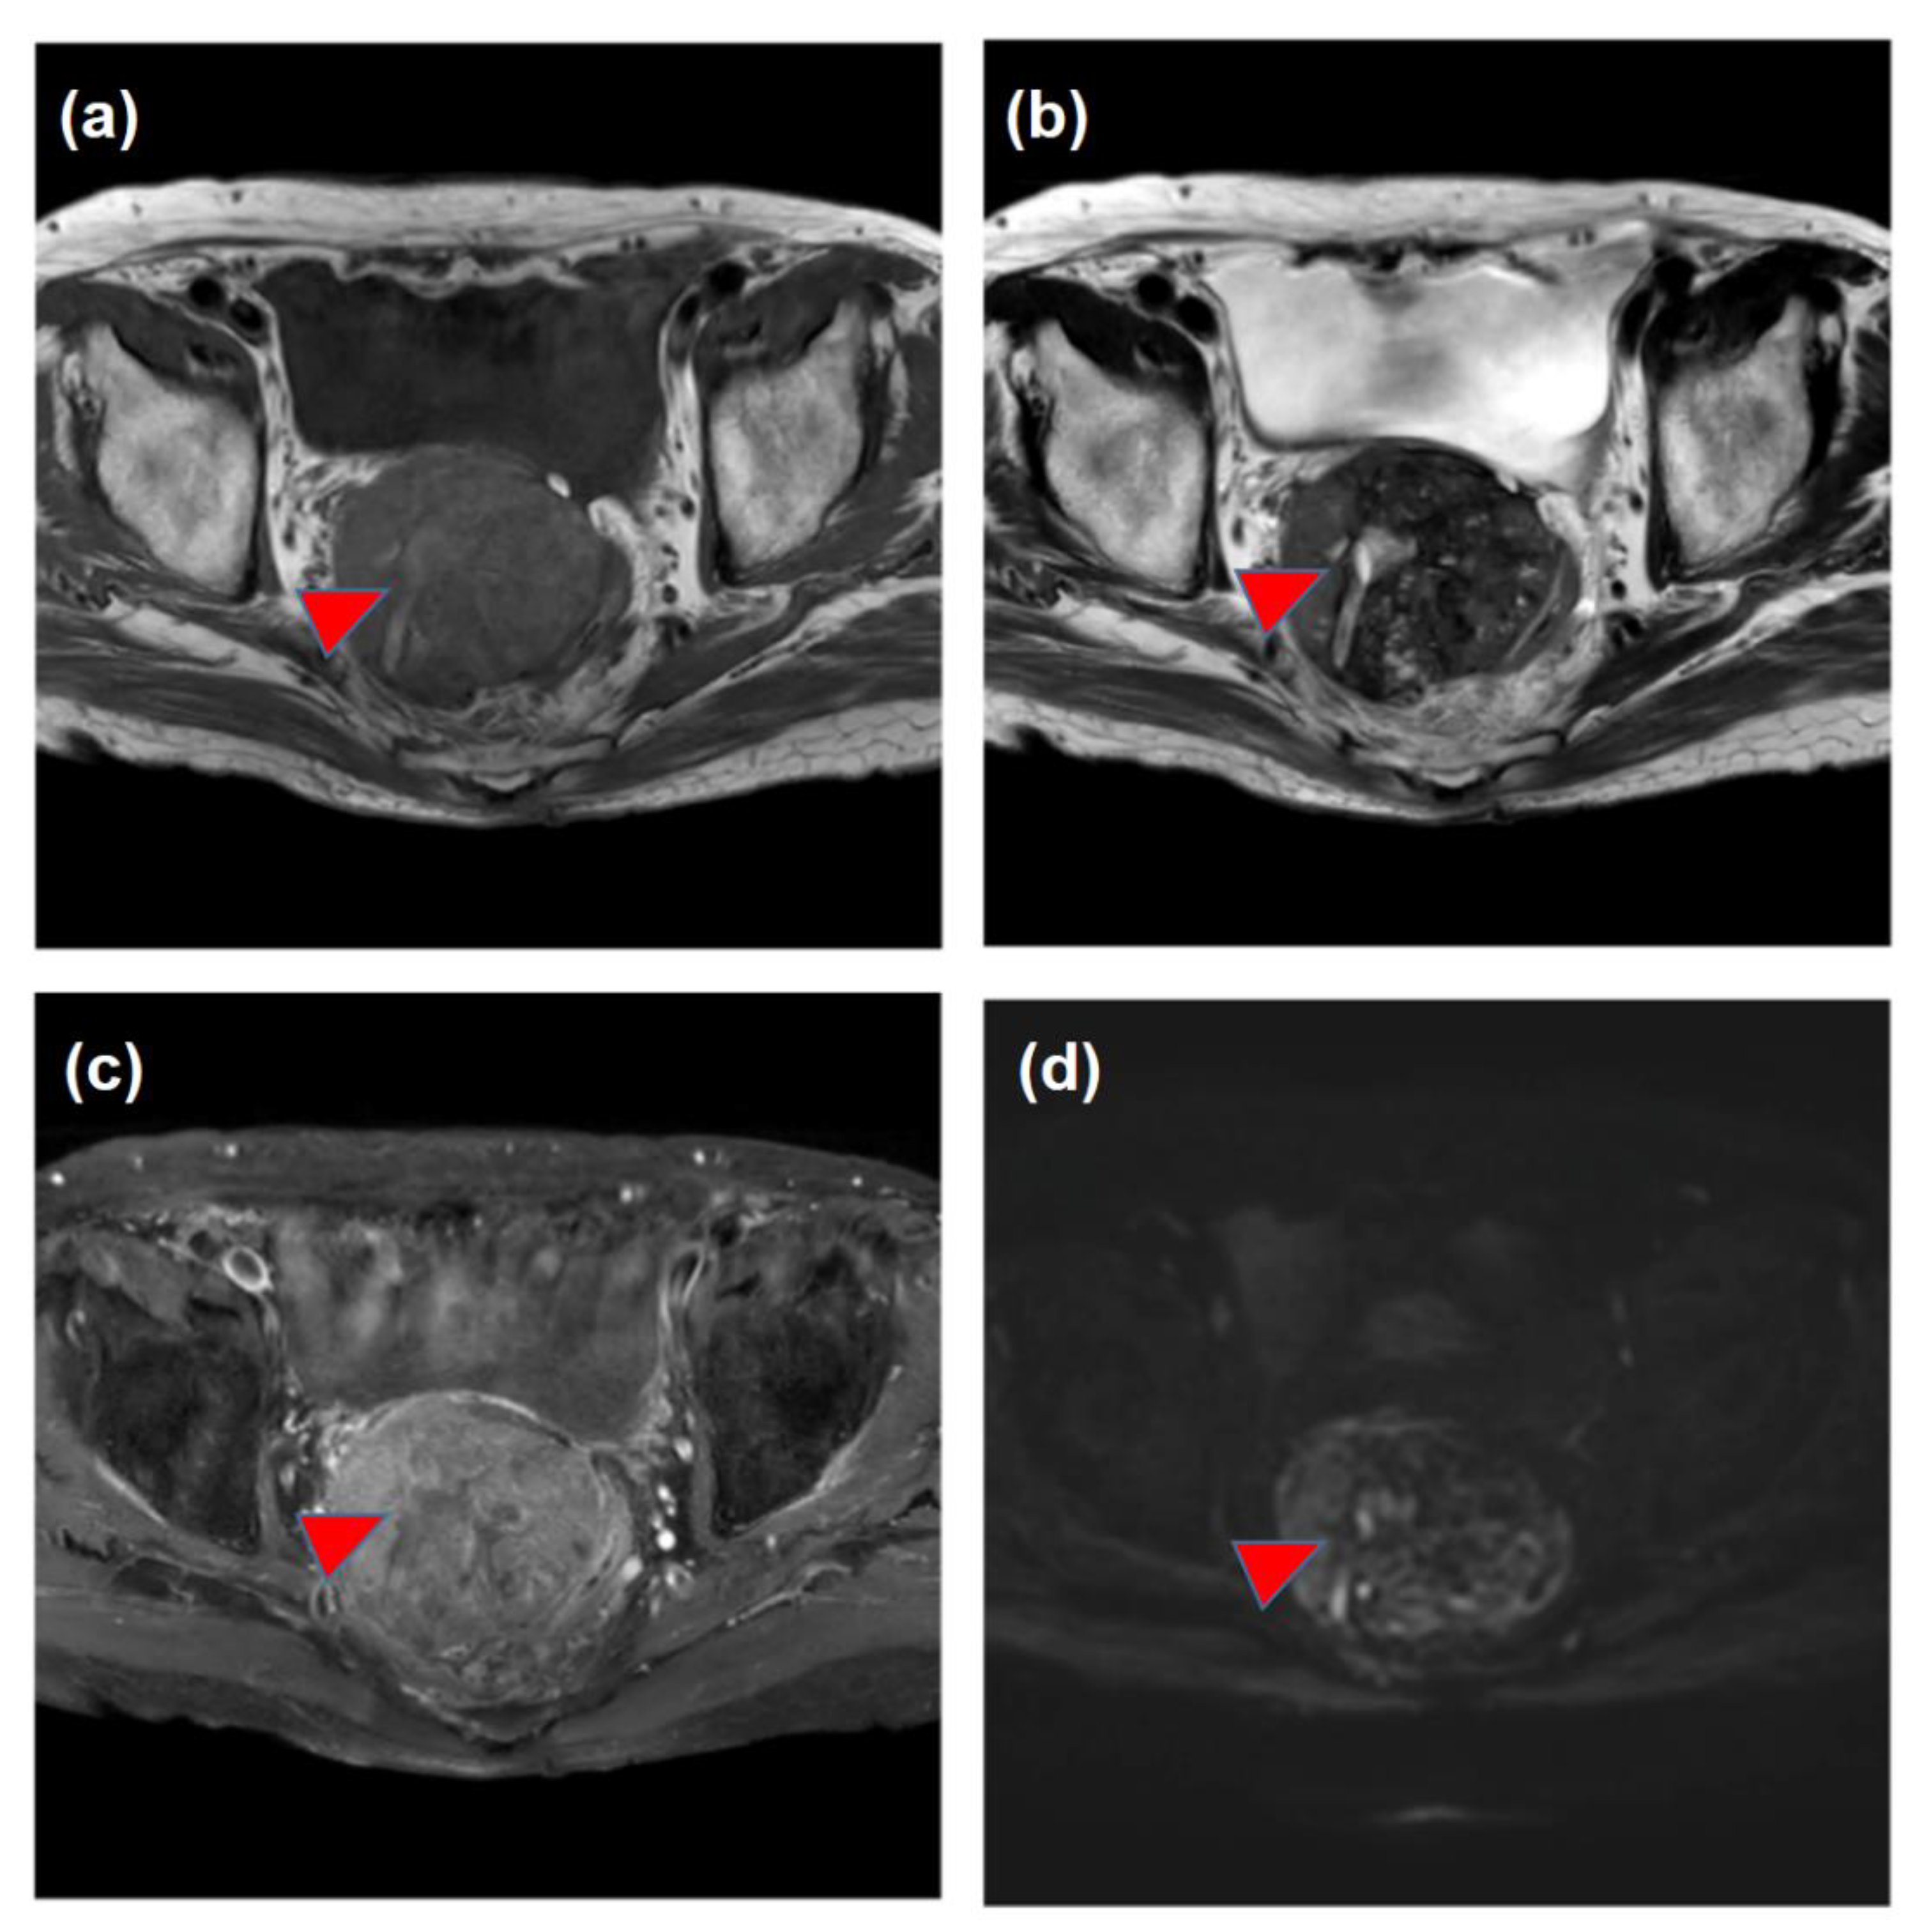

| March | Increase in the DCP and detection of the pelvic tumor Medical interview revealing mild constipation | |

| X | May | The histological diagnosis of pelvic metastasis of HCC |

| August–October | 3D-CRT (prescribed dose for the gross tumor: 60 Gy in 30 fractions) | |